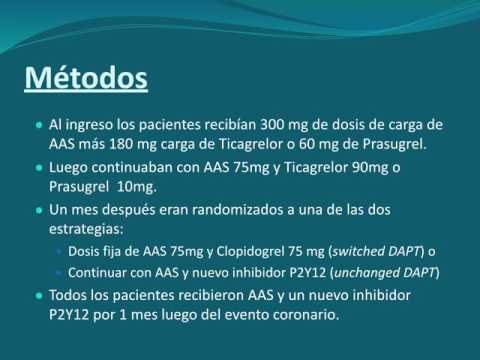

Beneficios del cambio de la doble antiagregación posterior a un SCA. Dra. María Laura Mori. Residencia de Cardiología. Hospital C. Argerich. Buenos Aires